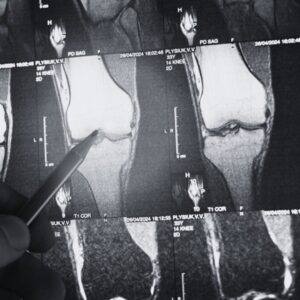

Read MoreClick Here to Watch the Video on YouTube Healthy cartilage lets your knees glide, bend, and bear weight without pain. But unlike skin or muscle, cartilage owns only…